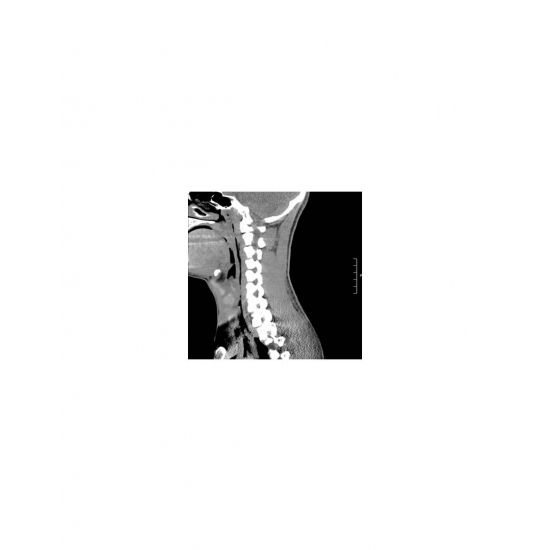

| Odynophagia In A Collegiate Baseball Player - Page #3 | |||